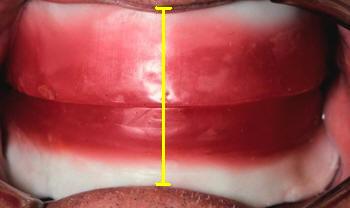

- La distancia entre la línea de los cuellos dentales y el plano

oclusal nos determinará el alto de los dientes antero superiores

|